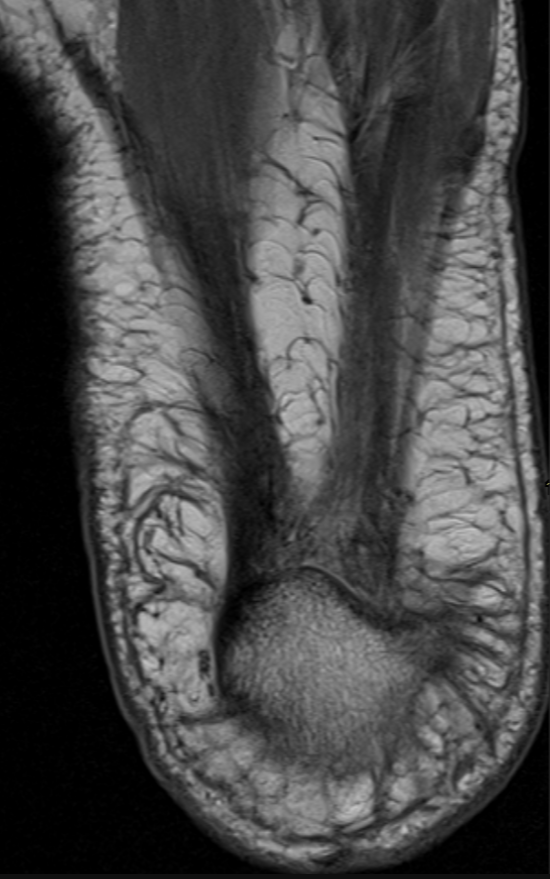

Plantar Fascia Anatomy